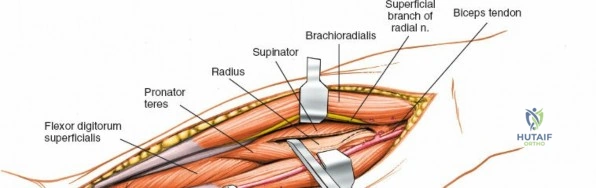

Exposing the proximal third of the radius requires extreme vigilance due to the proximity of the posterior interosseous nerve. The key anatomical landmark here is the insertion of the biceps tendon. Follow the biceps tendon distally to its insertion on the bicipital tuberosity of the radius. A small bursa lies just lateral to the tendon; incise this bursa to gain initial access to the proximal radial shaft. Because the radial artery lies superficial and medial to the tendon at this level, all deep dissection must remain strictly lateral to the biceps tendon.

The proximal radius is draped by the supinator muscle. The PIN passes directly through the belly of the supinator. To protect the nerve, the forearm must be fully supinated. Supination dynamically rotates the radius, carrying the insertion of the supinator anteriorly and simultaneously displacing the PIN laterally and posteriorly, safely away from the surgical field.

With the forearm fully supinated, identify the broad insertion of the supinator on the anterior aspect of the radius. Incise the supinator directly along the line of its insertion onto the bone. It is critical to detach the muscle by dividing its insertion sharply at the bone, rather than splitting the muscle belly, which would risk cutting the PIN.

Proceed with strict subperiosteal dissection, elevating the supinator laterally off the bone. This is one of the rare instances in orthopedic surgery where the safety gained by staying in a subperiosteal plane completely outweighs the theoretical vascular damage to the bone caused by periosteal stripping. The elevated supinator muscle belly now acts as a protective cushion for the PIN.

Retractor Placement and Fixation Technique

Once the proximal radius is exposed, great care must be taken with retractor placement. Never place Hohmann or levering retractors blindly around the posterior surface of the radial neck. Because the PIN may touch the bone posteriorly in up to 25% of patients, a posteriorly placed retractor can easily crush the nerve against the radial cortex. Instead, use gentle right-angle retractors or place retractors only on the anterior and lateral aspects of the bone, utilizing the elevated supinator as a shield.